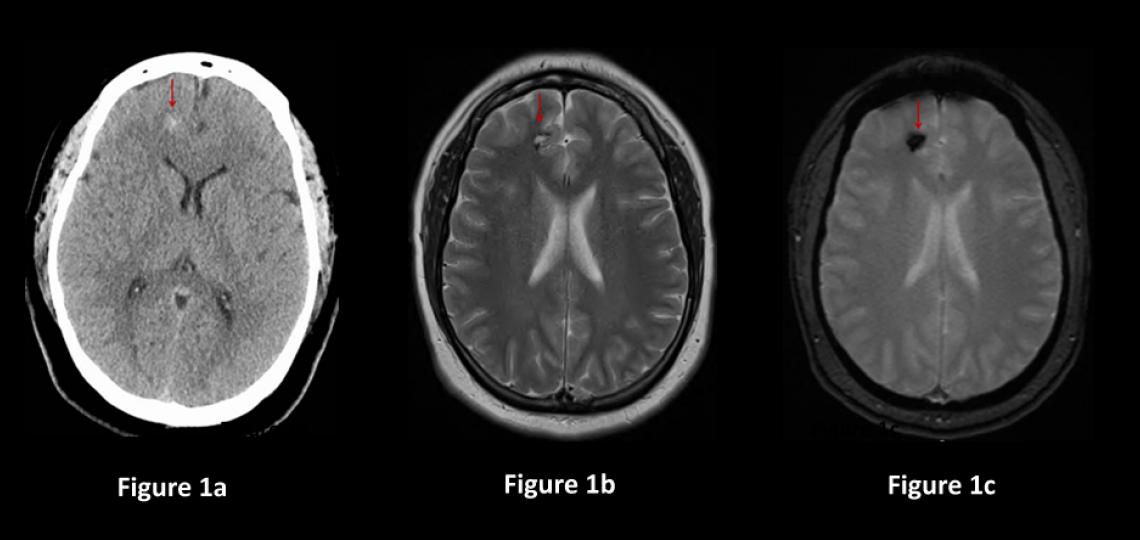

Direct removal of the cavernous malformation with surgery is the only known cure. Surgery is often recommended for cavernous malformations that are causing symptoms, grow on repeat imaging, bleed and are easily accessible by traditional neurosurgical methods with low risk of harming the surrounding brain (Figure2). The decision to treat cavernous malformations is nuanced and should be discussed between the patient and their cerebrovascular neurosurgeon.

Figure 2a: Brain CT scan in a patient having difficulty speaking shows a 3cm mass containing blood (red arrow). Figure 2b: Brain MRI showing the mass with blood inside (red arrow). Figure 2c: CT scan of the brain after surgery showing the cavernous malformation removed (red arrow) and less brain shift.